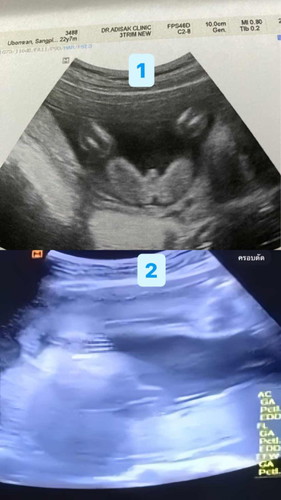

ไม่รู้น้องเพศไหนเลย หมอก็ไม่ชัวส์

รูปที่1ซาวด์ตอนอายุครรภ์20สัปดาห์หมอบอกว่าผู้ชาย 80% น้องอ้าขาโชว์เห็นชัด แต่หมอก็บอกไม่ชัวส์ รูปที่2ซาว์ล่าสุดอายุครรภ์26สัปดาห์หมอบอกว่าผู้หญิง เห็น3ขีด เปิดรูปที่1ให้หมอดูหมอก็บอกเหมือนผู้ชายแต่ก็ให้ไปลุ้นตอนคลอดอีกที แม่ๆๆพอดูออกไหมคะว่าเพศไหน #ซาวด์อยู่คลีนิคนะคะ